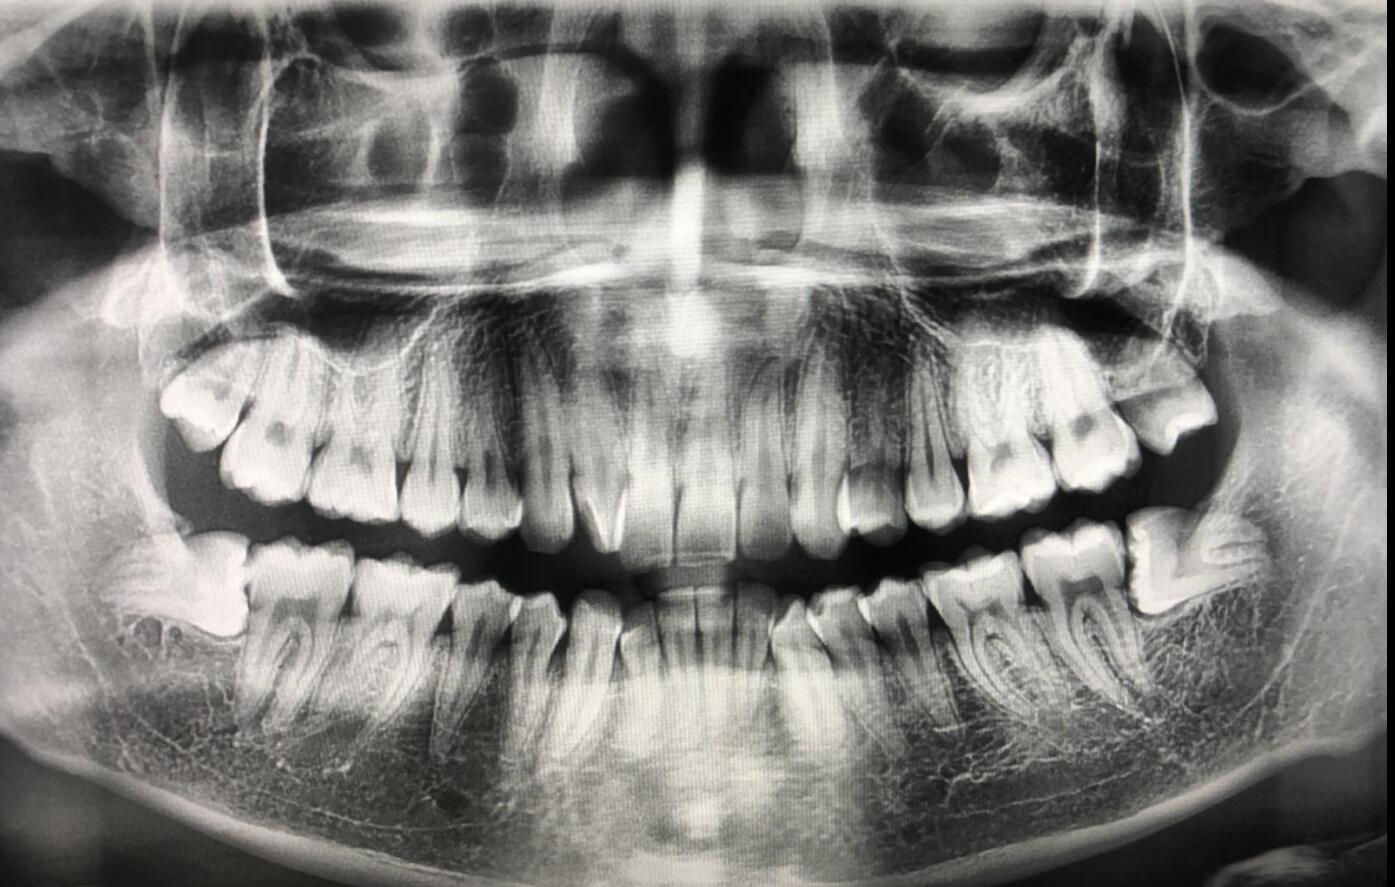

自己也没有猜想到,我的牙齿居然长成这样!

我又去了牙医诊所,医生给我的口腔里拍了片子,我的智齿长得很奇怪,其他的牙齿都是往上生长的,而我的智齿是横向生长的,虽然有一种对称的美丽,不过看上去就是医疗难度比较大。